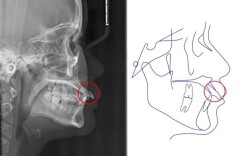

在硬件设施方面,郑州中心医院正畸科紧跟国际技术前沿,引进了全套数字化正畸诊疗系统,其中包括德国Sirona口内扫描仪,可替代传统取模,实现3分钟精准获取牙齿数据,提升患者舒适度;美国KaVo CBCT三维影像设备,能清晰显示牙根、牙槽骨及颌骨关系,为复杂病例的诊断提供精准依据;3D打印技术可快速制作个性化矫治器、手术导板等,缩短治疗周期,科室还配备数字化方案设计软件,医生可在电脑上模拟牙齿移动全过程,提前预测治疗效果,让患者更直观地了解矫正方案。

诊疗项目覆盖全年龄段各类牙齿畸形问题,儿童早期矫治针对3-12岁儿童,通过功能性矫治器(如MRC、罗慕)干预地包天、牙齿拥挤等问题,引导颌骨正常发育,降低后期矫正难度;青少年矫治以传统金属托槽、陶瓷托槽为主,结合自锁托槽技术,缩短复诊间隔,提升矫正效率;成人矫治注重美观与功能协调,提供隐形矫正(隐适美、时代天使)、舌侧矫正等隐形化选择,满足职场人士对美观的需求;针对骨性畸形患者,科室联合正颌外科开展术前术后正畸,通过精准的牙齿移动为手术创造条件,实现面部形态与咬合功能的同步改善,还开展牙周病正畸联合治疗、种植体支抗技术等特色项目,为复杂病例提供解决方案。